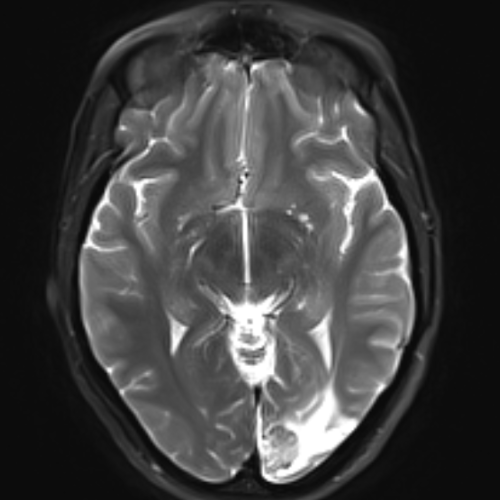

Brain

Brain & calvarial anatomy on CT/MRI

Cranial Nerves

Cranial nerves on MRI